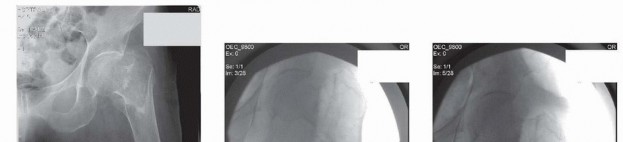

Peritrochanteric hip fractures are defined as extracapsular hip fractures, always involving the trochanter and frequently with extension into the subtrochanteric region. Medicare data indicates that as management of osteoporosis has improved, individual risk of sustaining a hip fracture has declined. 4 However, with an aging population, the total number of hip fractures increases each year. According to a Medicare database, 786,717 hip fractures were reported between 1986 and 2005. These fractures account for approximately 20% of Medicare claims. These fractures require operative intervention to achieve stable fracture fixation to allow immediate patient mobilization. ## ANATOMY The intertrochanteric region of the hip is notable for the anatomic transition from the femoral neck to the femoral shaft. The angle subtended by the femoral neck and long axis of the femoral shaft in the coronal plane (the neck-shaft angle) is usually between 120 and 135 degrees in adults. Studies have shown that this angle tends to decrease slightly with age. The average femoral neck is anteverted between 10 and 15 degrees with respect to the femoral shaft. 15 The peritrochanteric region of the femur is composed of multiple thickenings of trabecular bone distributed in compressive and tensile groups.5 The thickest and most structural are the primary compressive trabeculae located along the posterior medial aspect of the femoral neck and shaft, also known as the calcar. Multiple muscle groups attach to this region of the femur: Iliopsoas: attaches to the lesser trochanter and exerts a flexion and external rotation force to the hip Abductors and short external rotators: attach to the greater trochanter Adductors: attach to the femoral shaft distal to the peritrochanteric region The blood supply to the peritrochanteric region of the femur is rich and abundant. The medial and lateral femoral circumflex arteries supply the cancellous bone of the trochanteric region through muscle attachments at the vastus origin and the insertion of the gluteus medius. ## PATHOGENESIS In the elderly population, most peritrochanteric fractures are caused by a fall onto the lateral aspect of the hi Numerous factors, such as structurally weak bone, lack of subcutaneous padding, and slowed protective reflexes lead to increased risk of hip fracture in the elderly population. Pathologic lesions in the peritrochanteric region are not uncommon and may lead to fractures after relatively minor trauma. Young patients who sustain peritrochanteric fractures are typically victims of high-energy trauma. In these cases, the fracture must be approached differently, with an attitude toward anatomic restoration of joint mechanics. ## NATURAL HISTORY Almost all peritrochanteric hip fractures will heal without intervention. However, owing to the pull of the musculature in this region, the fracture will heal in gross malalignment, leading to subsequent functional limitations. 17 Early operative intervention of these fractures is undertaken to restore anatomic alignment and ensure that patients are mobilized quickly. Early fixation has been demonstrated to decrease incidence of pressure sores, pneumonia, and 30-day mortality. ## PATIENT HISTORY AND PHYSICAL FINDINGS It is important to elicit the cause of the patient's fall, as many falls in the elderly population that result in hip fractures are due to medical comorbidities. Elderly patients should be carefully evaluated and treated for rhabdomyolysis, dehydration, urinary tract infection, and malnutrition. In cases of preexisting poor mobility, consider deep vein thrombosis, and in anticoagulated patients it may be appropriate to obtain brain imaging. Complaints of hip pain before falling may indicate a preexisting pathologic process that requires further evaluation. A thorough whole-body musculoskeletal examination of the patient is necessary because of the high incidence of associated fractures (especially of the wrist and proximal humerus) in the elderly population sustaining hip fractures from simple falls. In cases of visible head trauma, cervical spine imaging can obviate prolonged cervical collar immobilization. Examination of the soft tissue overlying the lateral hip, sacrum, and heels is necessary to ensure that no pressure ulcers or abrasions have occurred in these areas. The classic physical finding in a patient with a peritrochanteric hip fracture is a shortened, externally rotated lower extremity. Passive logrolling of the leg will elicit pain. This may be an especially helpful finding in occult hip fractures with no obvious fracture deformity. 403 ## IMAGING AND OTHER DIAGNOSTIC STUDIES Plain radiographic anteroposterior (AP) pelvis and cross-table lateral images of the injured hip should be obtained initially. AP and lateral views of the femur, including the knee joint, should be obtained both to assess the femoral bow as well as to evaluate the femoral canal in the event that an intramedullary device is required. A traction radiograph (radiograph taken with firm manual traction and internal rotation of the leg) will provide more information on the fracture pattern and will allow a better comparison to the uninjured hip ( FIG 1A,B). Alternatively, an obturator oblique view of the pelvis can allow for this comparison without requiring additional analgesic medication. A fine-cut (2 mm) computed tomography (CT) scan with reconstruction images (sagittal and coronal) set to bone windows may help assess the fracture when ipsilateral femoral neck or other fractures are suspected. Magnetic resonance imaging (MRI) is the modality of choice to assess for the presence of an occult peritrochanteric hip fracture in the setting of significant hip pain and normal radiographs ( FIG 1C).

### FIG 1 • A. AP radiograph of an AO/OTA type 31-A1 pertrochanteric hip fracture. B. Traction radiograph; note the reduction seen with traction. C. MRI scan of a painful right hip showing an occult peritrochanteric fracture (arrow) not seen on plain radiographs. D. Lateral radiograph of an AO/OTA type 31-A3 intertrochanteric fracture. Note the displacement of this high-energy fracture, occurring in a young patient.